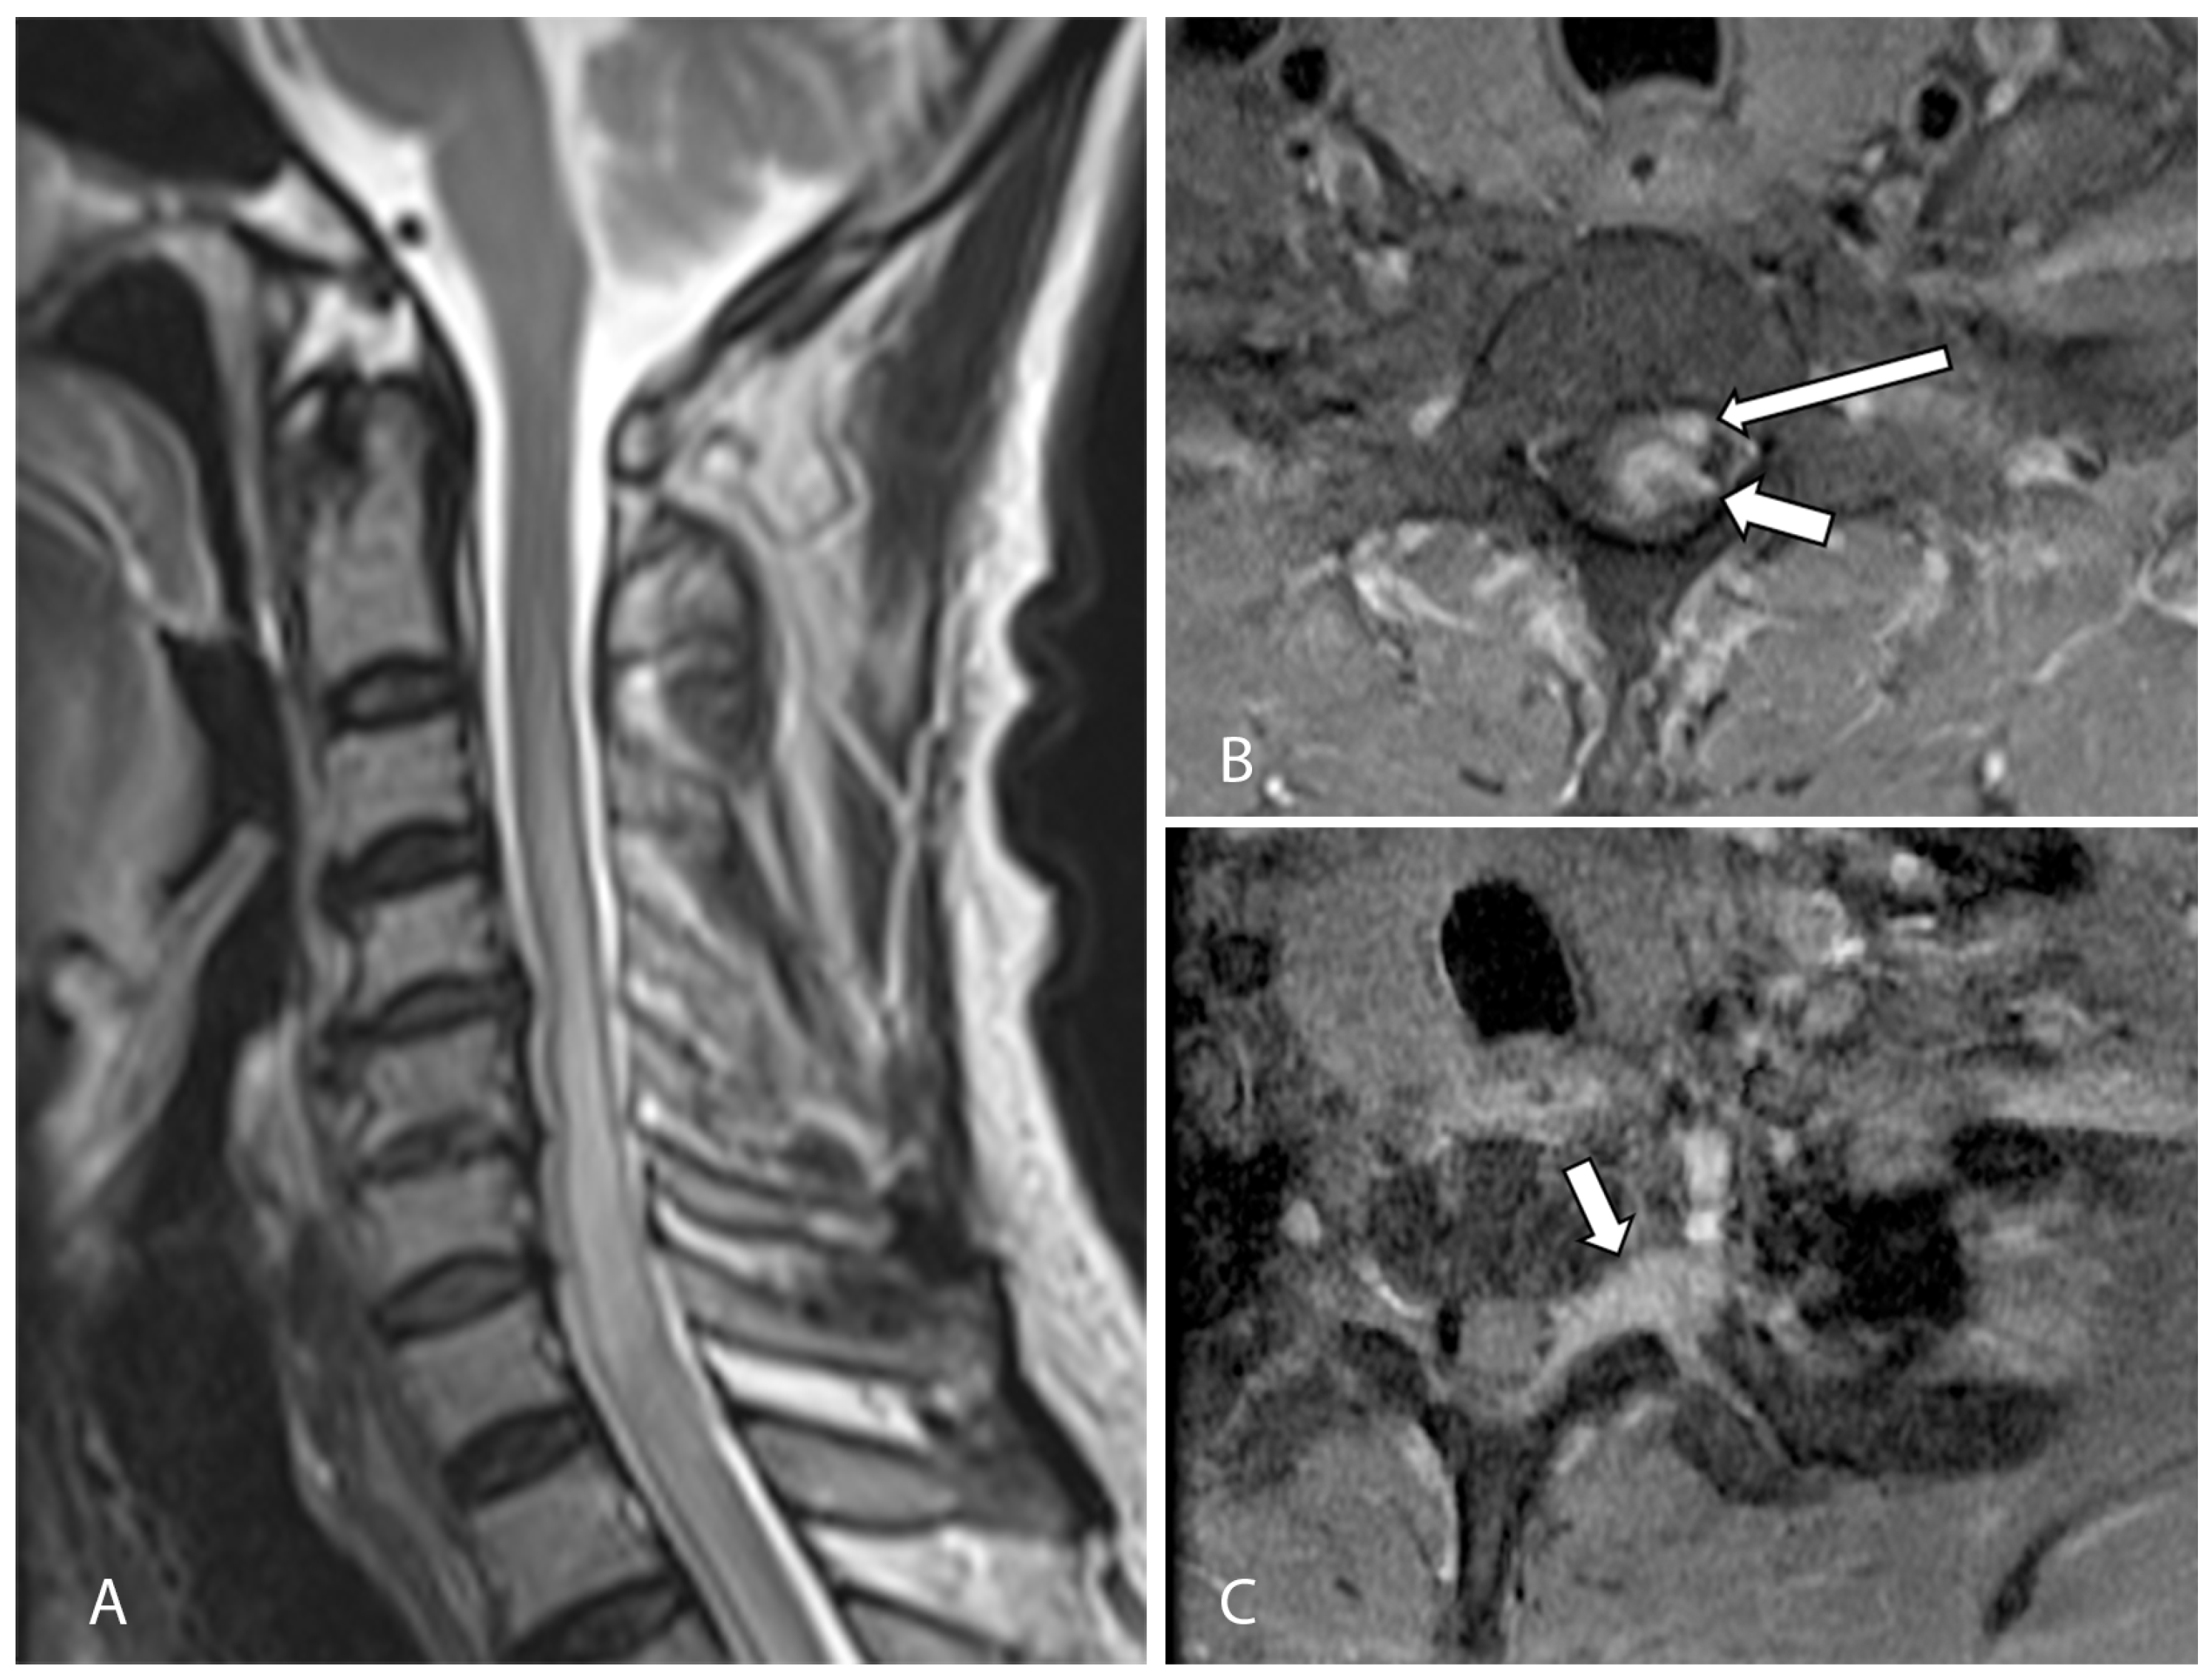

Magnetic resonance imaging (MRI) of his cervicothoracic spine and left brachial plexus demonstrated a 1.3 × 0.7 × 0.8 cm intraspinal mass centered at the level of T1 on the left. This lesion was heterogeneous and infiltrative, with poorly defined margins. It had an iso- to hypointense T2-weighted signal and demonstrated heterogeneous contrast enhancement. It appeared predominantly intramedullary in location with associated expansion and edema of the spinal cord. However, there was also thickening and enhancement along the left T1 nerve root with expansion of the left neural foramina, as well as a nodular enhancing focus which appeared extramedullary in location (Figure 1). On the basis of these initial clinical and imaging findings, the working diagnosis was that of an infective or inflammatory process resulting in leptomeningeal and perineural disease, with the differential diagnosis including secondary metastatic deposits or an underlying primary central nervous malignancy. However, an MRI brain study, as well as computed tomography of the thorax, abdomen, and pelvis, was unremarkable, with no other masses or metastatic disease elsewhere. Lumbar puncture was performed, and cerebrospinal fluid analysis did not yield any positive microbiological culture, viral DNA PCR results, or any malignant cells.

Figure 1.

(A) Initial sagittal T2-weighted MRI of the cervical spine showed long segment cord signal change/edema and cord expansion. (B) Axial T1-weighted, fat-suppressed, contrast-enhanced MRI of the cervical spine shows an enhancing intramedullary lesion at the level of T1 (short arrow). There is also a nodular enhancing focus which appeared extramedullary in location (long arrow). (C) Axial T1-weighted, fat-suppressed, contrast-enhanced MRI of the brachial plexus at a level slightly inferior to (B) shows abnormal thickening and enhancement along the left T1 nerve root (arrow), suspicious for perineural disease spread.